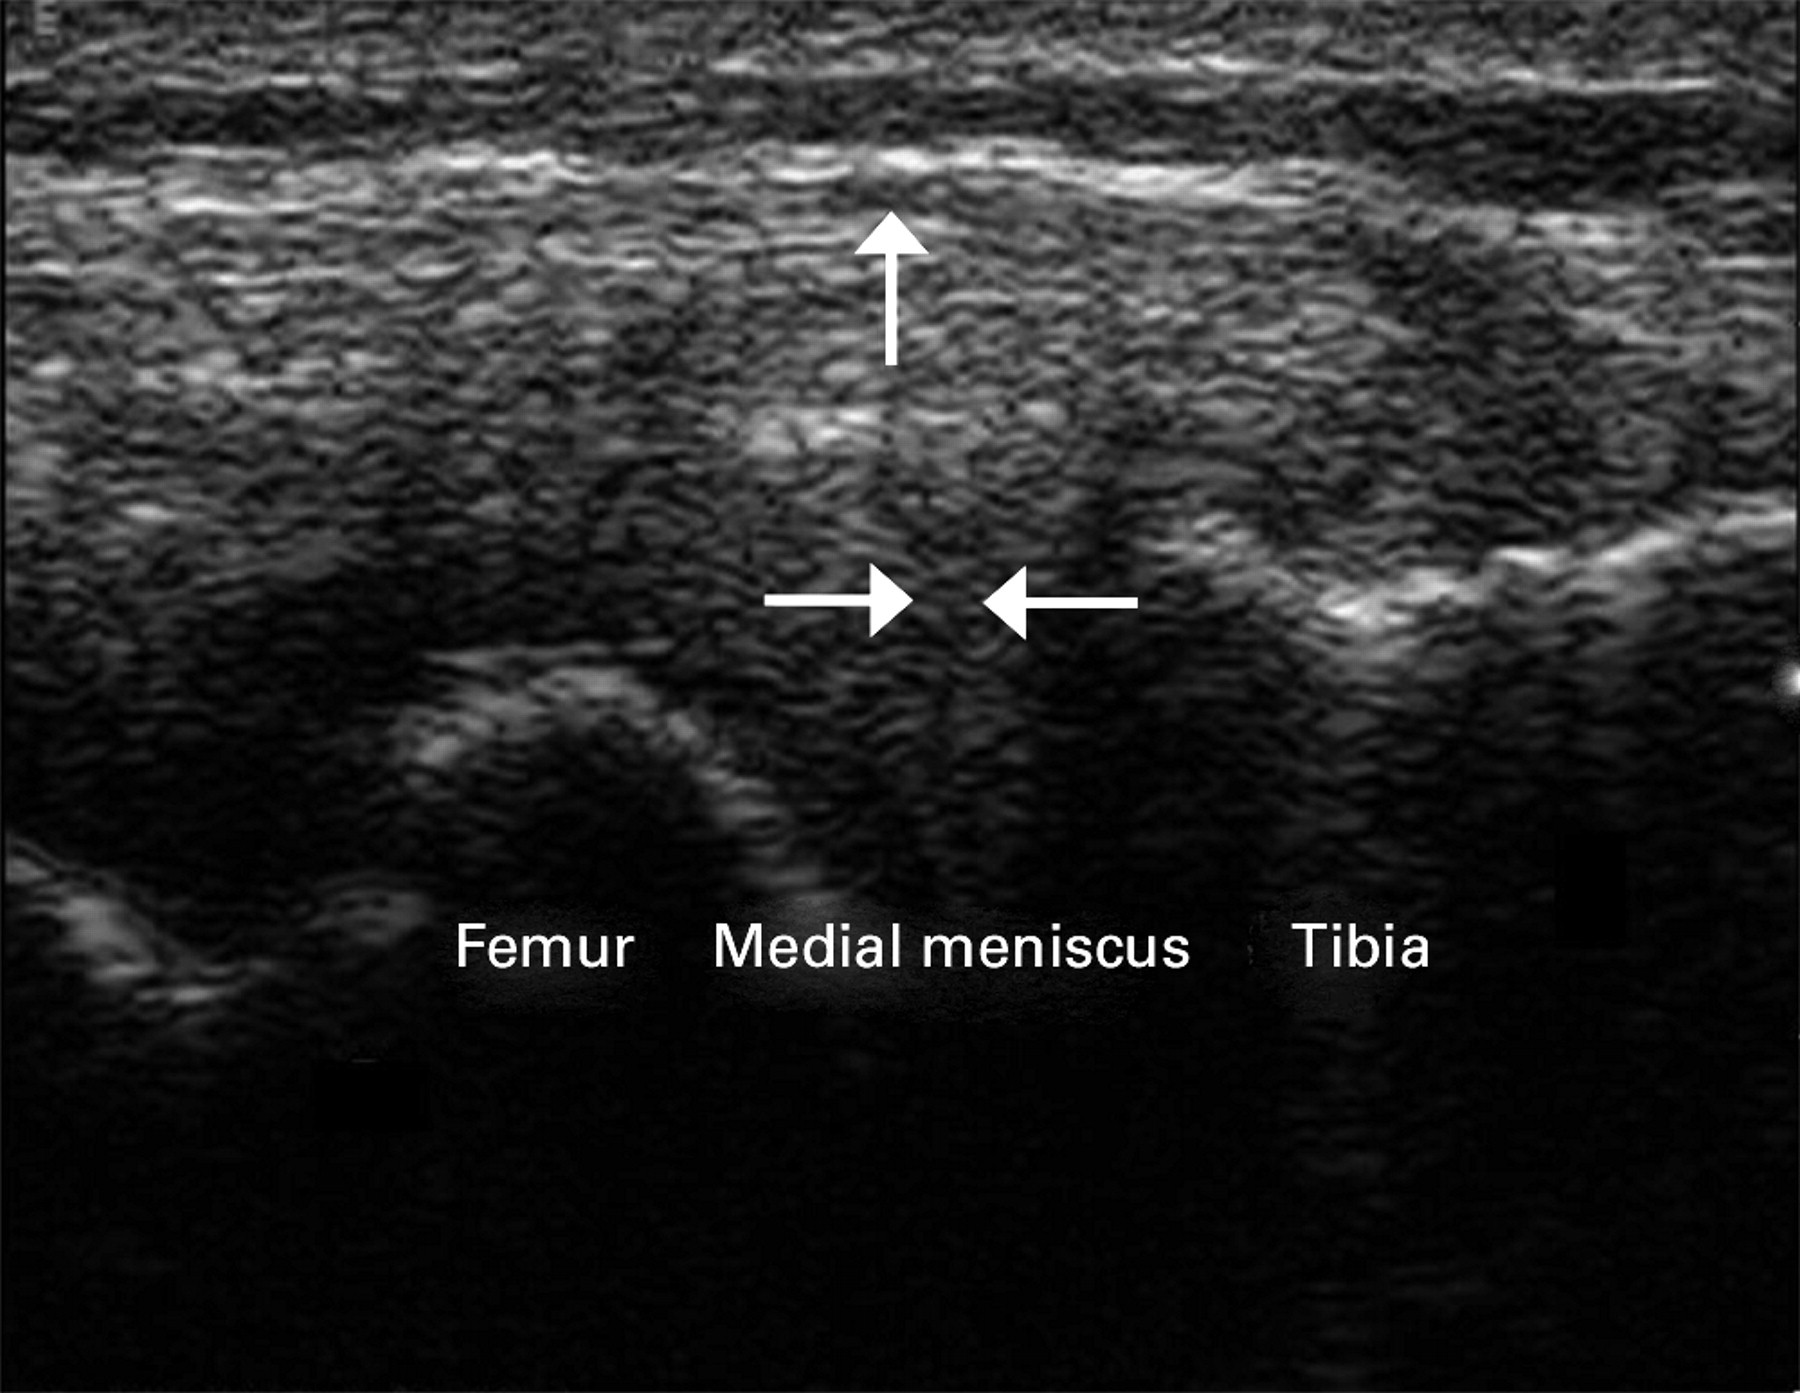

2/ Phương pháp thứ hai là quan sát chuyển động ra ngoài (đẩy ra) của sụn chêm khi kiểm tra động gối